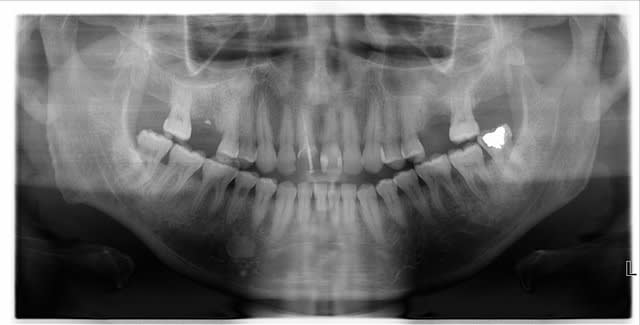

Il présente donc ce pédicule gingival dont le point d'attache semble se situer au niveau de la papille 44 45. D'après l'interrogatoire, il a commencé à apparaître fin juin et ne cesse de grandir. Le patient m'a dit qu'il avait eu la même chose il y a deux ans, qu'une dentiste lui avait retiré sans autre examen. Il n'a pas mal mais souhaitait qu'on lui enlève comme la dernière fois.

Il n'a pas de douleur à la palpation, une légère sensibilité à la percussion sur 44 45. Le test de vitalité est positif sur 45 mais pas sur 44.

Je ne suis pas sûre qu'il s'agisse d'un épulis gingival vu l'aspect de la muqueuse...

tu dois avoir un point d'entrée quelque part et la gencive prolifère en regard de la lésion...

Epulis on le retrouve chez les patientes ( il s'agit d'un patient) au maxillaire supérieur. Donc non...

A couper pour analyse.

Ce nodule est surement a mettre en rapport avec la resorption de la dent.

pas d'accord sur le terme "Epulis" .

Nodule gingival oui